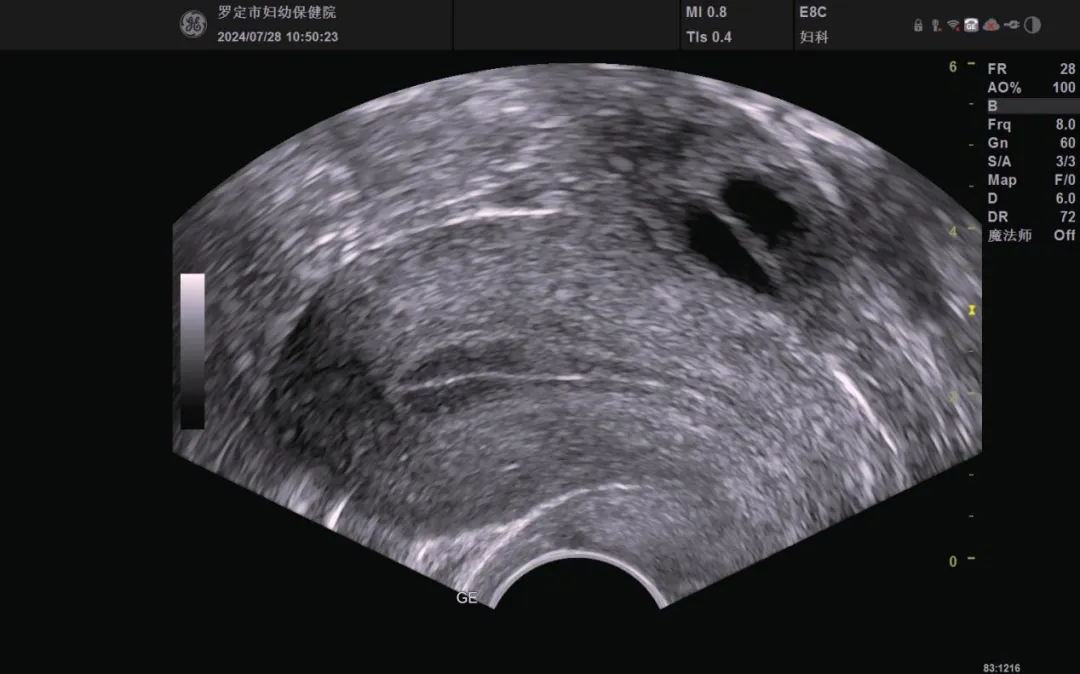

健康科普 | 好“孕”第一步——卵泡的超声监测